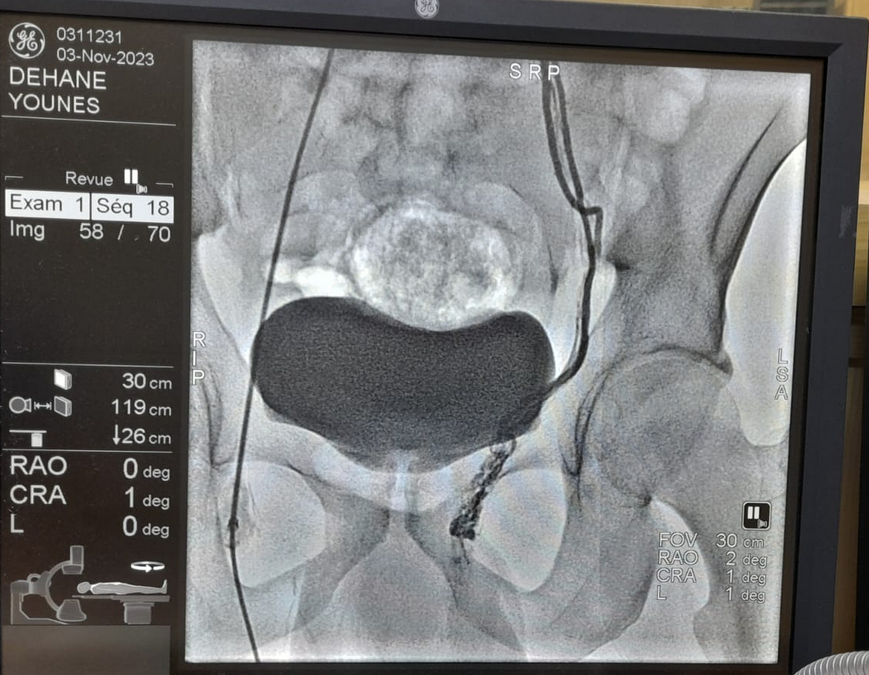

- بالمقابل العلاج بالاشعة التداخلية او ما يسمى ( القسطرة) يقوم بإجرائها اخصائي الاشعة التداخلية او جراحةالاوعية الدموية و القسطرة الطرفية تحت تخدير موضعي على طاولة جراحية خاصة ( غرفة القسطرة) او في غرف العمليات الجراحية و ذلك بإدخال القسطرة عن طريق الوريد الفخذي او وريد الذراع الايمن وصولا الى المكان اللازم

- يتم حقن كمية قليلة من صبغة اليود و استخدام الاشعة السينة و التى تمكن ااطبيب المعالج من المشاهدة الواضحة لجميع الاوردة و بالتالي علاجها بشكل كامل مناسب حسب موقعها و حجمها

-هذا العلاج يعتبر الامثل و الافضل لأنه يمكن من رؤية جميع الاوردة الفرعية للوريد المنوي و ذلك عن طريق عمل خارطة وريدية شاملة

يعتبر علاج دوالي الخصية بالقسطرة أحدث طرق العلاج لدوالي الخصية حيث يتم غلق الوريد المتسبب في الدوالي باستخدام الملفات الحلزونية أو من خلال حقن مادة صمغية تعمل على غلق الوريد حيث يتم ذلك تحت مخدر موضعي، وتستغرق هذه القسطرة حوالي ساعة، ويتم العلاج من خلال فتحة دقيقة 2 مم وبالتالي لا تترك علامات جراحية على الجل

ـ أكثر اكتمالا لأن هناك العديد من أوردة التصريف التي يمكن رؤيتها بشكل جيد بواسطة الأشعة السينية الأولى (تصوير الأوردة المنوية).